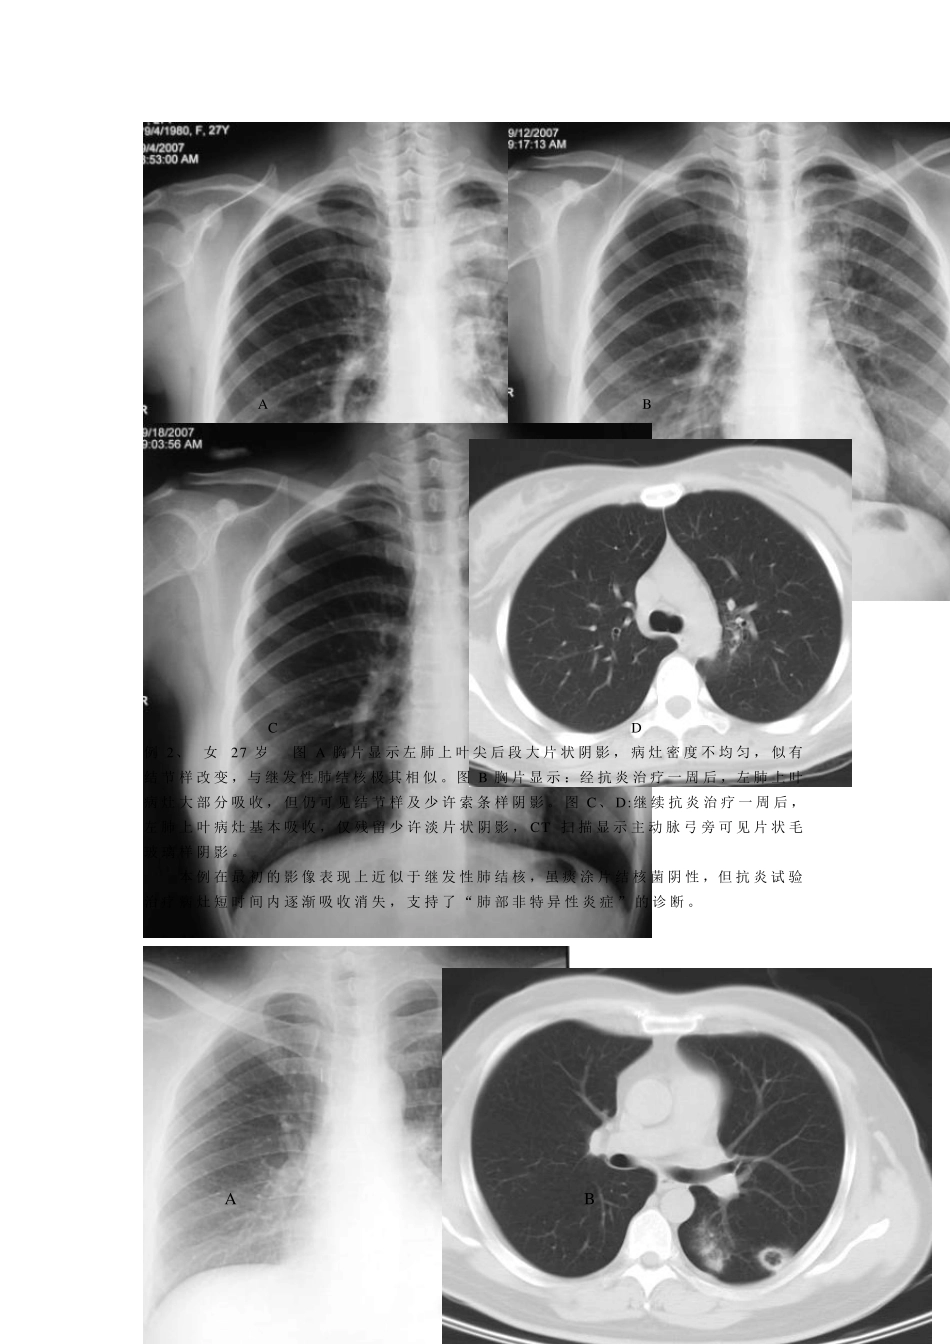

1 一、 与肺结核表现极其相似的肺部炎性病变 尽 管 肺 结 核 的 表 现 多 具 有 一 定 特 点 , 但 部 分 肺 部 炎 症 性 病 变 在 影 像 上 却往 往 与 肺 结 核 的 表 现 极 其 相 似 , 虽 然 两 者 病 理 解 剖 学 构 成 迥 然 不 同 , 但 呈 现相 同 影 像 表 现 者 在 临 床 屡 见 不 鲜 。 因 此 , 肺 部 炎 症 性 病 变 应 该 是 临 床 诊 断 中最 常 见 和 最 需 要 与 肺 结 核 病 变 鉴 别 的 疾 病 , 尤 其 是 继 发 性 肺 结 核 。 在 影 像 诊 断 中 , 鉴 于 肺 结 核 和 肺 部 炎 症 性 病 变 病 理 变 化 的 不 同 , 通 常 是立 足 于 评 价 肺 部 影 像 以 多 种 形 态 共 存 的 特 点 来 确 定 继 发 性 肺 结 核 的 诊 断 , 而以 相 对 均 一 性 的 特 点 来 诊 断 非 特 异 性 炎 性 病 变 。 由 于 引 起 肺 部 炎 症 性 病 变 的病 原 很 多 ,包 括 细 菌 、病 毒 和 霉 菌 等 ,仅 从 影 像 学 角 度 有 时 也 往 往 难 以 确 诊 ,应 该 密 切 结 合 临 床 表 现 及 各 种 相 关 实 验 室 检 查 结 果 进 行 诊 断 , 必要 时 可进 行抗感染试验 性 治疗, 以 进 行 动态 观察。 现 将在 影 像 表 现 上 与 肺 结 核 病 变 极 其 相 似 的 肺 部 炎 症 性 病 变 等 例举如下: A B C 例1、男 30 岁 图A 胸片显示两 肺 弥漫性 粟粒结 节影 ,以 两 中 下肺 野分 布为甚,部 分结 节有 融合 表 现 。 图B、 C:CT 扫描显示两 中 下肺 弥漫分 布的 粟粒结 节影 , 呈 对 称性 较均 匀分 布, 结 节边缘大多 数清楚, 仅 基底段结 节有 融合 倾向, 并可见 小叶间隔增厚。 本例在 影 像 诊 断 上 首先考虑为血行 播散性 肺 结 核 , 但 各 种 肺 结 核 相 关 检 查 均 阴性 ,最 后经血清肺 军团菌 抗体检 测多 组指标阳性 , 最 终诊 断 为“ 军团菌 肺 炎 ” 。 2 A B C D 例2、 女 27 岁 图A 胸片显示左肺上叶尖后段大片状阴影,病灶密度不均匀,似有结节样改变,与继发...